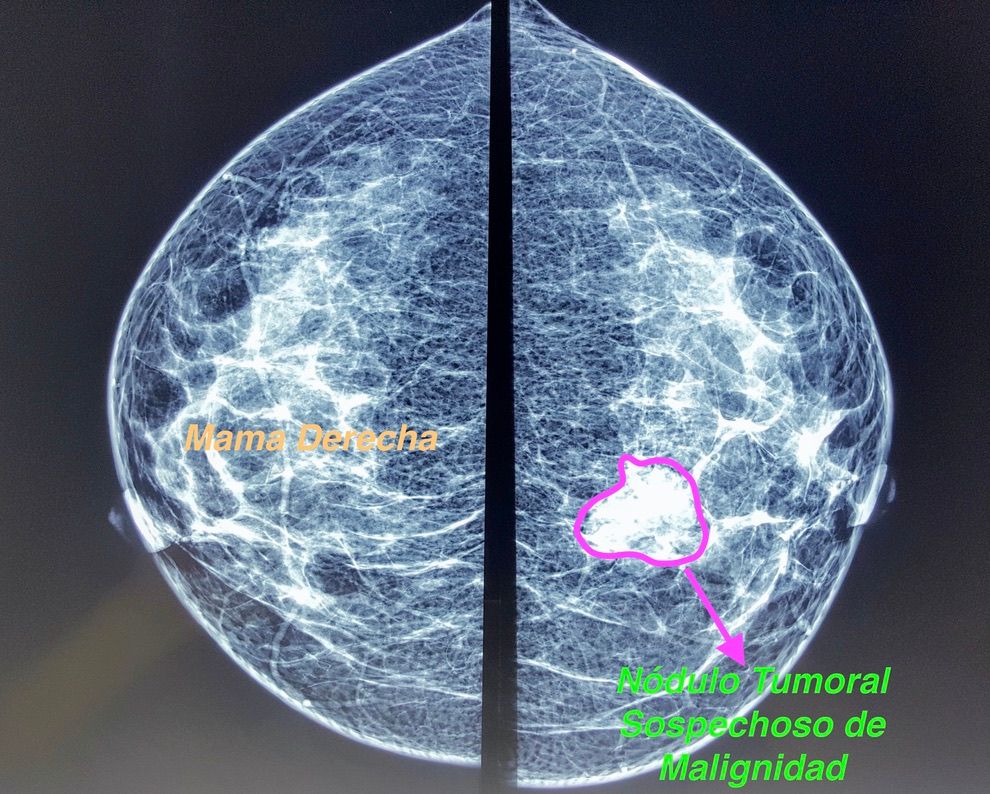

Tumor de mamas

Tumorectomia de mama (Cuadrantectomia)

Tumorectomia de mama con vaciado axilar

Tumores mamarios

Biopsia de mama por marcaje

Biopsia mamaria

Biopsia trucut de mama

Biópsia quirúrgica de mama